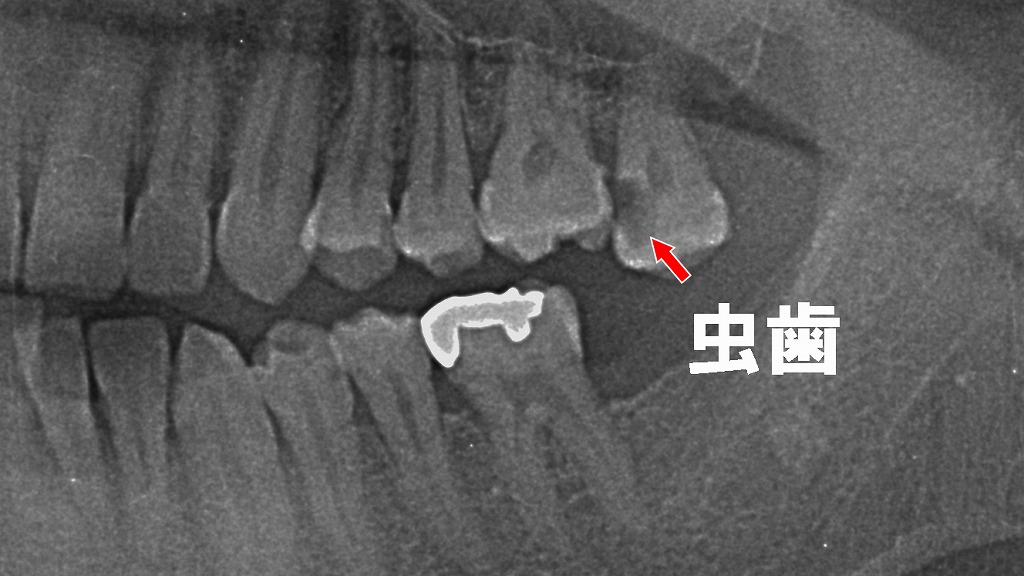

X線画像の矢印部分が虫歯で、噛み合わせの異常が大きく関係しています。

🤔歯の傾斜による咬合不調と虫歯のリスク

歯が傾斜することで隣在歯との辺縁隆線に段差が生じ、噛むたびに食片が圧入されやすい状態となっています。清掃が困難になるため、矢印部では**隣接面う蝕(虫歯)**が進行している所見が確認できます。歯列不正やわずかな位置異常であっても、虫歯や歯周病の原因となることがあります。